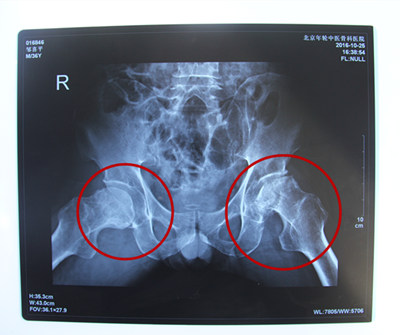

诊断结果:双侧股骨头缺血性坏死伴左侧扁平髋、左侧股骨头半脱位

病情描述: 患者于5年前无明显诱因出现左髋腹股沟区及外上方疼痛,行走劳累后加重,就诊于当地诊所,以腰椎间盘突出症治疗,疗效不佳。一年前因疼痛加重,就诊于当地医院,经影像检查后确认为股骨头坏死,间断给予口服抗炎止疼药等对症处理,病情时好时坏,两个月前患者病情加重。却苦于四处求医无法根治,花光了家里的存款,依旧不见好转。站立机会走进内蒙古,通过当地的残联了解到患者的情况。

经特殊批准让他得到了站立计划的全额救助,来到北京年轮中医骨科医院接受治疗。经年轮股骨头医师会诊后决定对股骨头坏死病变区进行左髋关节滑膜切除、清理并修正松解;同时取髂骨进行骨移植微创治疗,并辅以特制中医中药调理病况,由康复医师指导日常髋关节功能的恢复。